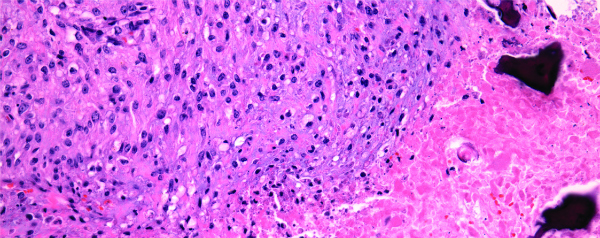

Met behulp van een genetisch gemanipuleerde variant van de bacterie Clostridium novyi is het onderzoekers gelukt om tumoren te bestrijden bij ratten, honden en mensen. De bacterie leeft uitsluitend in zuurstofarme omgevingen en gedijt daarom goed in tumoren, waarvan de kern vaak weinig zuurstof bevat. Eenmaal binnen kan de bacterie de tumor van binnenuit ‘opeten’.

C. novyi is normaal gesproken giftig voor mensen. Het gif van dit organisme kan zorgen voor weefselschade en kan uiteindelijk zijn gastheer doden. Amerikaanse onderzoekers hebben nu echter een genetisch gemanipuleerde variant van de bacterie gemaakt: Clostridium novyiNT, waarbij het gif ontbreekt. Deze aangepaste bacterie zou kunnen helpen bij het bestrijden van tumoren.

De bacterie gedijt alleen in zuurstofarme omgevingen. Dat maakt hem uitstekend geschikt om kanker te bestrijden, omdat de kern van tumoren vaak zeer weinig zuurstof bevatten.  Als de bacterie aanwezig is in de tumor kan hij deze langzaam afbreken.

Nadeel is wel dat de bacterie de randen van de tumor (die meer zuurstof bevatten) met rust laat. Wetenschappers hopen dan ook de behandeling te kunnen combineren met bestraling of chemotherapie.